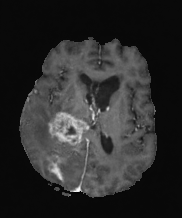

| non-CE T1w (Input) | Residual U-Net (PM) | RF Baseline | PMRF (ours) | CE T1w (GT) |

We qualitatively evaluate the top-performing Residual U-Net (Posterior Mean), RF baseline, and PMRF models (with a patch-overlap of 32 for all and integration steps for the RF baseline as well as the PMRF model) on the held-out test set. For a set of representative cases, Figure 3 compares the non-CE T1w input, Res. U-Net (equivalent to PM), RF baseline, our two-stage PMRF, and the ground truth CE T1w image. Example 1 depicts a metastases patient, example 2 a high-grade glioma patient, and example 3 a meningioma patient. Across these test cases, the Res. U-Net output accurately localizes lesions and captures their overall enhancement intensity but appears overly smooth, and muted in rim heterogeneity and fine texture. The Stage 2 PMRF refinement consistently sharpens lesion boundaries, reinstates subtle vascular and margin details, and restores characteristic enhancement patterns, yielding synthetic images nearly indistinguishable from true post-contrast scans. However, Stage 2 can only refine what the posterior-mean predictor already suggests. If a subtle rim, micro-metastasis, or vessel enhancement is entirely suppressed in Stage 1, Stage 2 has no signal to resurrect it; its perturbations stay within a narrow neighborhood of the Stage 1 output. In contrast, the RF baseline directly predicts the CE signal from the perturbed non-CE image. However, this comes with the limitation of not predicting the CE strength faithful or missing subtle details as in examples 2 and 3.